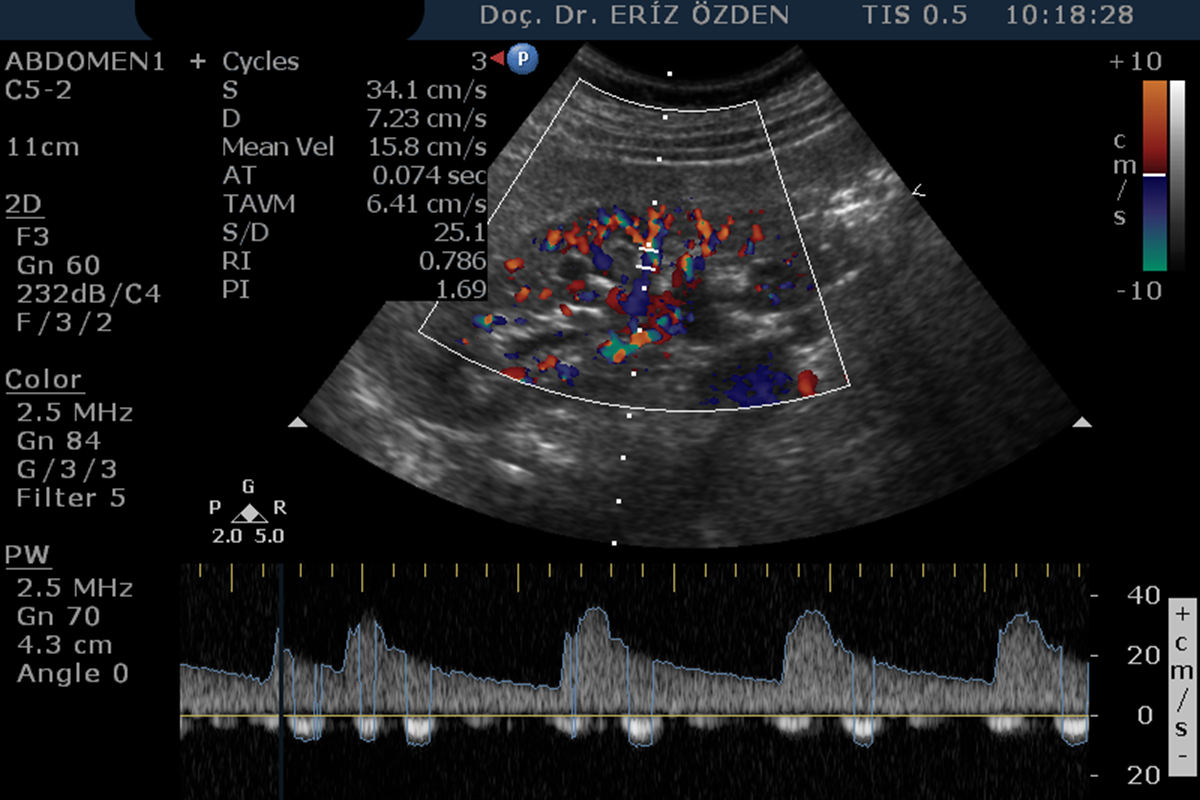

Böbreğe giden atardamarlarda darlık olması durumunda, tansiyon yüksekliği (hipertansiyon) ortaya çıkabilir. Böbrek damarlarının ayrıntılı incelenmesi, darlıkların, tıkanıkların saptanması, böbrek kanlanması hakkında bilgi edinilmesi için Renkli Doppler Ultrason kullanılır. İnceleme sırasında bağırsak gazları görüntüyü bozabileceğinden, hastanın aç olarak gelmesi gereklidir.